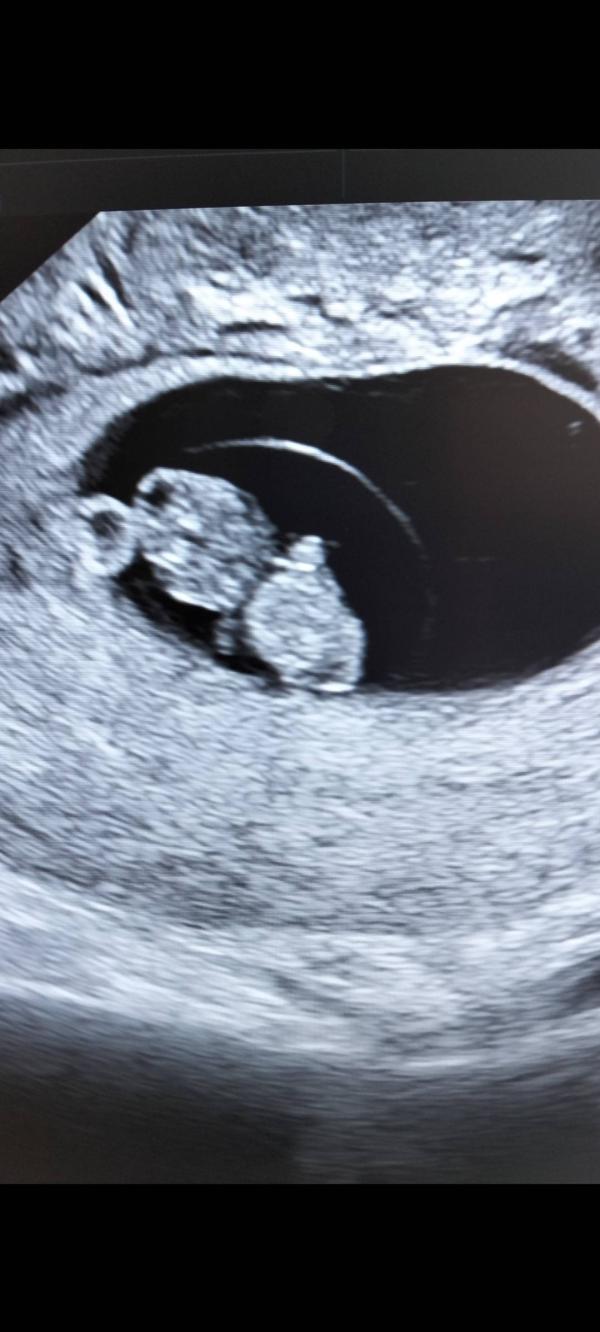

Привет, девочки. Еду с УЗИ, вот он человечек мой любимый😍💕

Спасибо большое. Только ко врачу теперь завтра, переживаю. Поставили гематому ретрохориальную